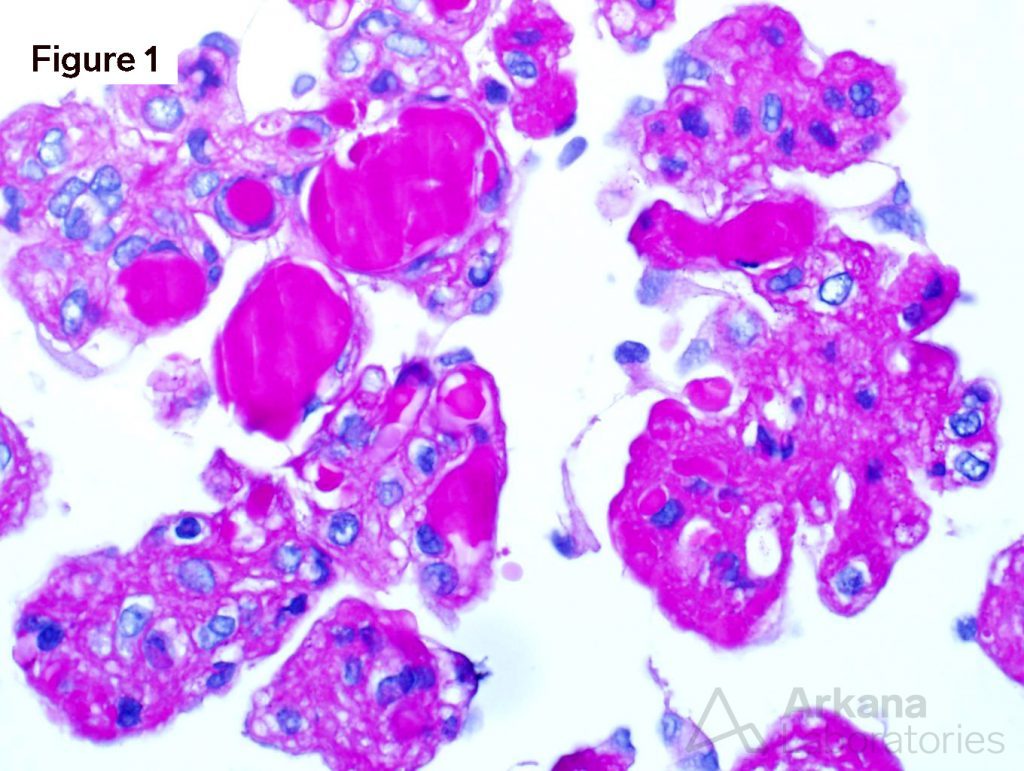

A diagnosis of Waldenström macroglobulinemia depends on a significant monoclonal IgM spike, which is evident in blood tests and malignant cells consistent with the disease in bone marrow biopsy samples. Blood tests show the level of IgM in the blood and the presence of proteins, or tumor markers, that are the key signs of Waldenström macroglobulinemia. A bone marrow biopsy provides a sample of bone marrow, usually from the lower back of the pelvis bone. The sample is extracted through a needle and examined under a microscope. A pathologist identifies the particular lymphocytes that indicate Waldenström macroglobulinemia. Flow cytometry may be used to examine markers on the cell surface or inside the lymphocytes.